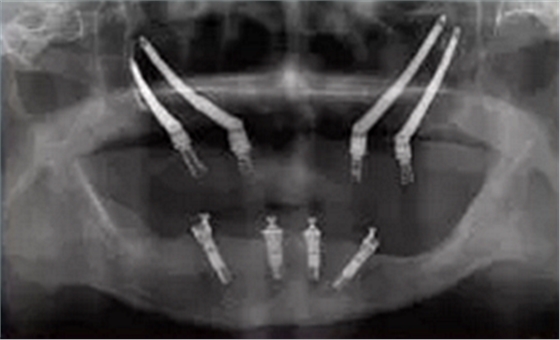

圖 3 雙顴種植體植入術(shù)后全景片

Figure 3 Radiographic of post?surgery of quad zygomatic implants placement

前牙區(qū)剩余骨量嚴(yán)重不足而無(wú)法植入常規(guī)種植體的患者, 不符合顴骨種植的經(jīng)典術(shù)式適應(yīng)癥。Bothur[16]等學(xué)者提出單側(cè)顴骨植入多枚種植體的可行性, 并分別于雙側(cè)顴骨各植入2枚和3枚種植體, 繼而提出雙側(cè)顴骨各植入2枚顴骨種植體的改良術(shù)式(zygomatic quad approach)[17, 18, 19, 20], 又稱之為雙顴種植體植入術(shù)(圖3)。該改良術(shù)式較經(jīng)典術(shù)式的適應(yīng)癥更為廣泛, 能獲得更加優(yōu)化的植體受力分布。但研究指出[21], 單側(cè)顴骨植入2枚種植體時(shí), 更容易出現(xiàn)種植體位置過(guò)近, 傷及眼球、眶下神經(jīng)血管等重要解剖結(jié)構(gòu), 引起嚴(yán)重的手術(shù)并發(fā)癥。 為了提高顴種植體植入手術(shù)的精準(zhǔn)性和安全性, 目前臨床上有學(xué)者使用計(jì)算機(jī)輔助手術(shù)導(dǎo)航技術(shù)來(lái)幫助完成手術(shù)(圖4 ~ 5)。